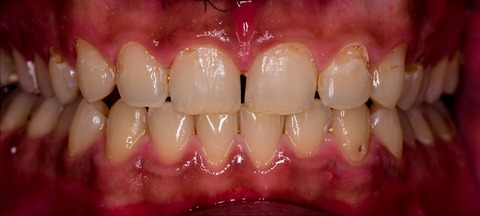

A 26-year-old female with severe crowding. Comprehensive orthodontic treatment was completed. Patients were amazed by the results.